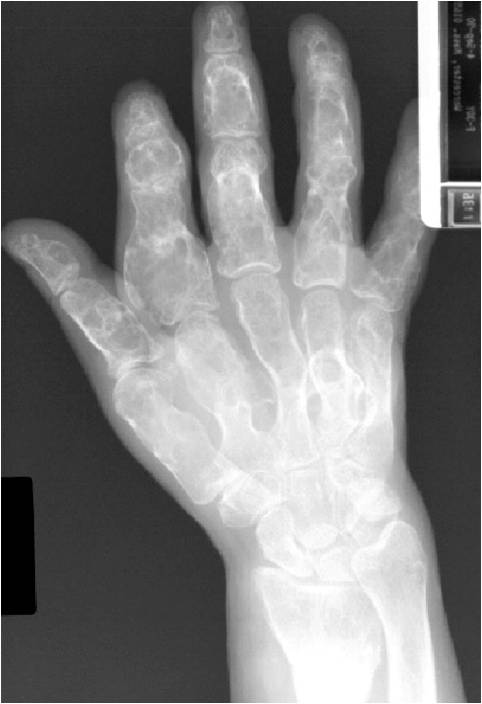

- 50% involve hands and feet (mostly phalanges)

- Localized, radiolucent defect usually with punctate calcifications

- Calcifications are typical but not always present

- Matrix may demonstrate various degrees of calcification

- Calcifications are stippled, punctate, popcorn like calcifications and “Ring and Arc” calcifications

- Cortex may be scalloped and thinned in the phalanges

- Geographic lytic lesion

- Expansile remodeling with thinned cortex

- Chondroid matrix with calcifications in majority of tumors

- Approximately 20% have limited or no calcifications